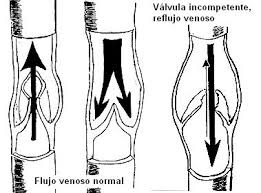

329 × 361 - gimolimpo.com

{"cb":3,"cl":9,"cr":9,"ct":3,"id":"xpk45dB8E7I8sM:","isu":"gimolimpo.com","itg":0,"ity":"jpg","oh":361,"ou":"http://www.gimolimpo.com/Paginas/feblectomia_archivos/image007.jpg","ow":329,"pt":"FEBLECTOMIA","rid":"ZemkA-aU5uHAnM","rmt":0,"rt":0,"ru":"http://www.gimolimpo.com/Paginas/feblectomia.htm","s":"óptima

relación

costo/beneficio","sc":1,"st":"Olimpo","th":235,"tu":"https://encrypted-tbn0.gstatic.com/images?q\u003dtbn:ANd9GcTGBYVUqIaQnxn14lGu1tBPjfbHVvdDHcHstHMXtyqikZScWr_ocw","tw":214}

379 × 281 - gimolimpo.com

{"id":"yi_QeHfQlQD5hM:","isu":"gimolimpo.com","itg":0,"ity":"jpg","oh":281,"ou":"http://www.gimolimpo.com/Paginas/feblectomia_archivos/image003.jpg","ow":379,"pt":"FEBLECTOMIA","rid":"ZemkA-aU5uHAnM","rmt":0,"rt":0,"ru":"http://www.gimolimpo.com/Paginas/feblectomia.htm","s":"Tipos

de

tratamiento","sc":1,"st":"Olimpo","th":193,"tu":"https://encrypted-tbn0.gstatic.com/images?q\u003dtbn:ANd9GcTl_DJI550zaYSZMH-miDVhWY4UK03LOi9ze-1B_FsuneyxG_grOQ","tw":261}

231 × 397 - gimolimpo.com

{"cl":3,"id":"Ofxp5Rburirp3M:","isu":"gimolimpo.com","itg":0,"ity":"jpg","oh":397,"ou":"http://www.gimolimpo.com/Paginas/feblectomia_archivos/image005.jpg","ow":231,"pt":"FEBLECTOMIA","rid":"ZemkA-aU5uHAnM","rmt":0,"rt":0,"ru":"http://www.gimolimpo.com/Paginas/feblectomia.htm","s":"Flebectomía

ambulatoria, es la safenectomía, modificada por el Dr. Oesch, suizo,

que consiste en efectuar la exéresis de la vena, sin lesionar los

tejidos

...","sc":1,"st":"Olimpo","th":294,"tu":"https://encrypted-tbn0.gstatic.com/images?q\u003dtbn:ANd9GcQTaZ5oRKfEvwuBOC5RWCE4GIQU2e4MrfYhpJMx2vBMlbt5qVXNew","tw":171}